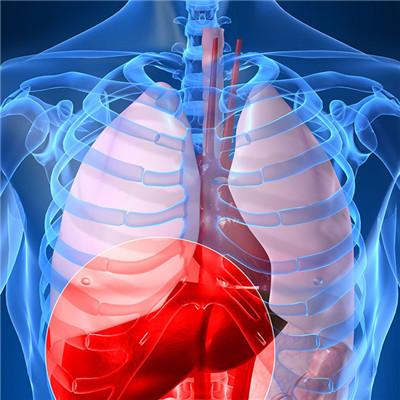

Many people will get liver disease. Usually, the patient's complexion will become very bad, and his face will become very bad. He has no strength all over the body. He has a cough, headache, fever, cold, abdominal pain, abdominal distension, low vision, and people will become very weak. He is easy to get angry, and his mouth will also have ulcers, Once the above symptoms, we must go to the hospital in time for examination and treatment, oral propionic acid solution, if you get liver disease for a long time, it is likely to cause hepatitis, will lead to cirrhosis, and finally lead to liver cancer, so we must pay attention to, do not delay the disease, the following is to introduce what symptoms of liver disease what

First, hepatitis A: the main symptoms of hepatitis A are: fear of cold, gastrointestinal symptoms, abdominal pain, diarrhea, high temperature, liver swelling and so on. The main route of transmission is fecal oral transmission, and the other is the transmission of sporadic cases in daily life.

Second: second, hepatitis B: hepatitis B is mainly divided into three types: including jaundice, its main symptoms are gastrointestinal symptoms, such as anorexia, greasy, nausea and vomiting, etc; The main symptom of non jaundice type is hepatomegaly; Chronic hepatitis B, its symptoms are dull face, spider nevus or liver palms and hepatomegaly.

Third: second, hepatitis B: hepatitis B is mainly divided into three types: including jaundice, its main symptoms are gastrointestinal symptoms, such as anorexia, greasy, nausea and vomiting, etc; The main symptom of non jaundice type is hepatomegaly; Chronic hepatitis B, its symptoms are dull face, spider nevus or liver palms and hepatomegaly.